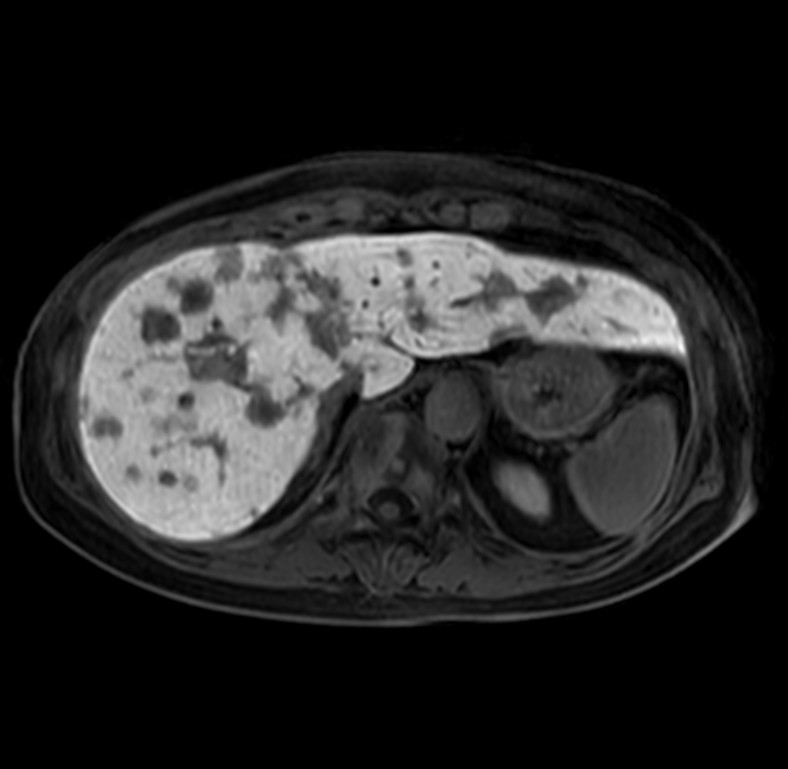

Axial Heavy T2w SSh FatSat